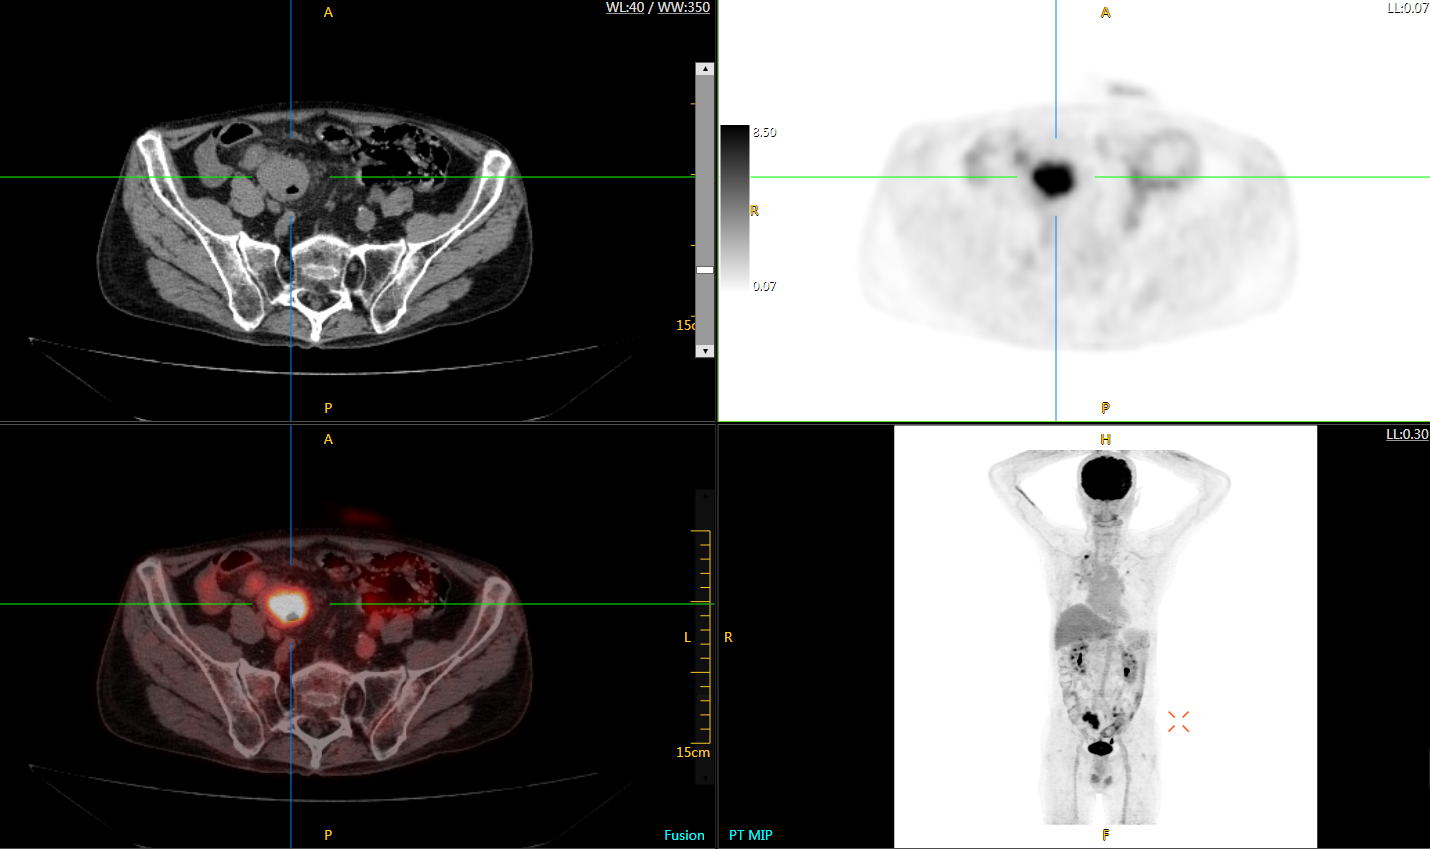

肺癌轉移及復發(fā)

患者男性,66歲,七年前發(fā)現(xiàn)右肺肺癌,其間手術兩次,共切除兩個肺葉,復查;

診斷意見,回腸轉移,右肺殘留部復發(fā)